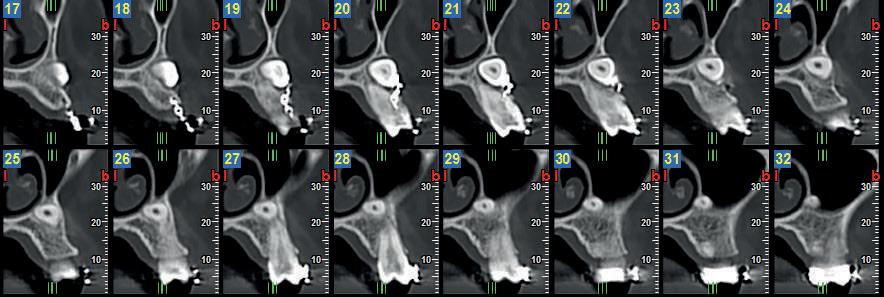

La diagnostica per immagini si avvale di tecniche 2D (Ortopanoramica dentale e full endorale) e 3D (3D Cone Beam Computed Tomography - CBCT).

La 3D CBCT consente la perfetta localizzazione, posizione, versione del canino incluso, la valutazione dei rapporti con gli elementi dentali limitrofi ed eventuali contatti di allarme con le strutture anatomiche critiche (seno mascellare, CNP, fossa nasale, forcazione del premolare superiore).

Le notizie fornite al clinico sono necessarie nella pianificazione della terapia di disinclusione, che può essere ortodontica e/o chirurgica.

Nel presente articolo presentiamo 3 casi di inclusione del canino superiore.

Fig 2 : stesso Paziente. Ricostruzione panorex.

Il 13 è incluso per ostacolo di eruzione relativo alla presenza di minuti denticoli (odontoma composto).

In emiarcata sinistra, come reperto collaterale, si osserva persistenza di 63 ed agenesia di 23.

Fig 3 - Fig 4 : Paz F. aa 12

Il 13 ed il 23 sono inclusi in posizione alta, mesioangolati, con associate ampie cisti follicolari.

Il 13 è visibile dalla sezione radiale 21 alla 26.

La cuspide di 13 è craniale al 12.

Le cisti follicolari assottigliano, e a destra in parte discontinuano, i tavolati corticali vestibolare e palatale.

Si rileva inoltre rizalisi di 12. 21. 22 relative alla estensione delle lesioni cistiche.

Fig 5 - Fig 6 : Paz F aa 16 Ricostruzione panorex e sezioni radiali dell’emiarcata sinistra.

- Il 23 è in trazione ortodontica per inclusione alta in posizione mesio-trasversa, contiguo al pavimento della fossa nasale sinistra ed al pavimento del seno mascellare sinistro.

L’apice radicolare di 23 si impegna nel pavimento del seno mascellare sinistro; la cuspide erompe in versione vestibolare, craniale all’apice radicolare di 24.